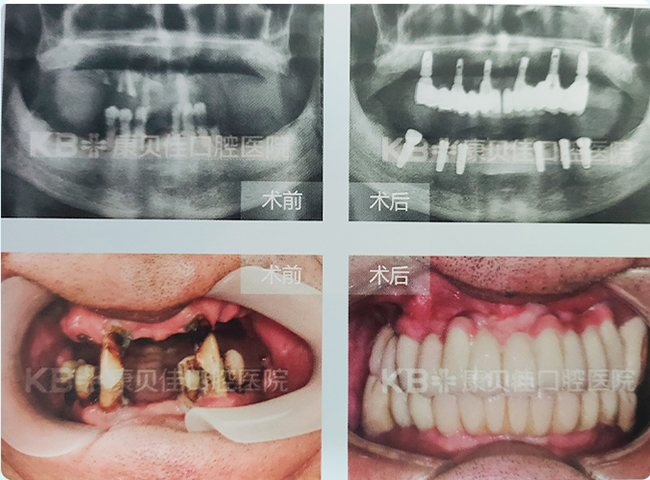

华先生 63岁

因长期吸烟导致全口牙松动、脱落,一日三餐都成了负担。后经人介绍到康贝佳拔除重度松动的牙,上颌种植6颗种植体后,下颌又种6颗种植体恢复了满口好牙。

治疗方案:

上颌种植6颗恢复半口 下颌种植6颗恢复半口